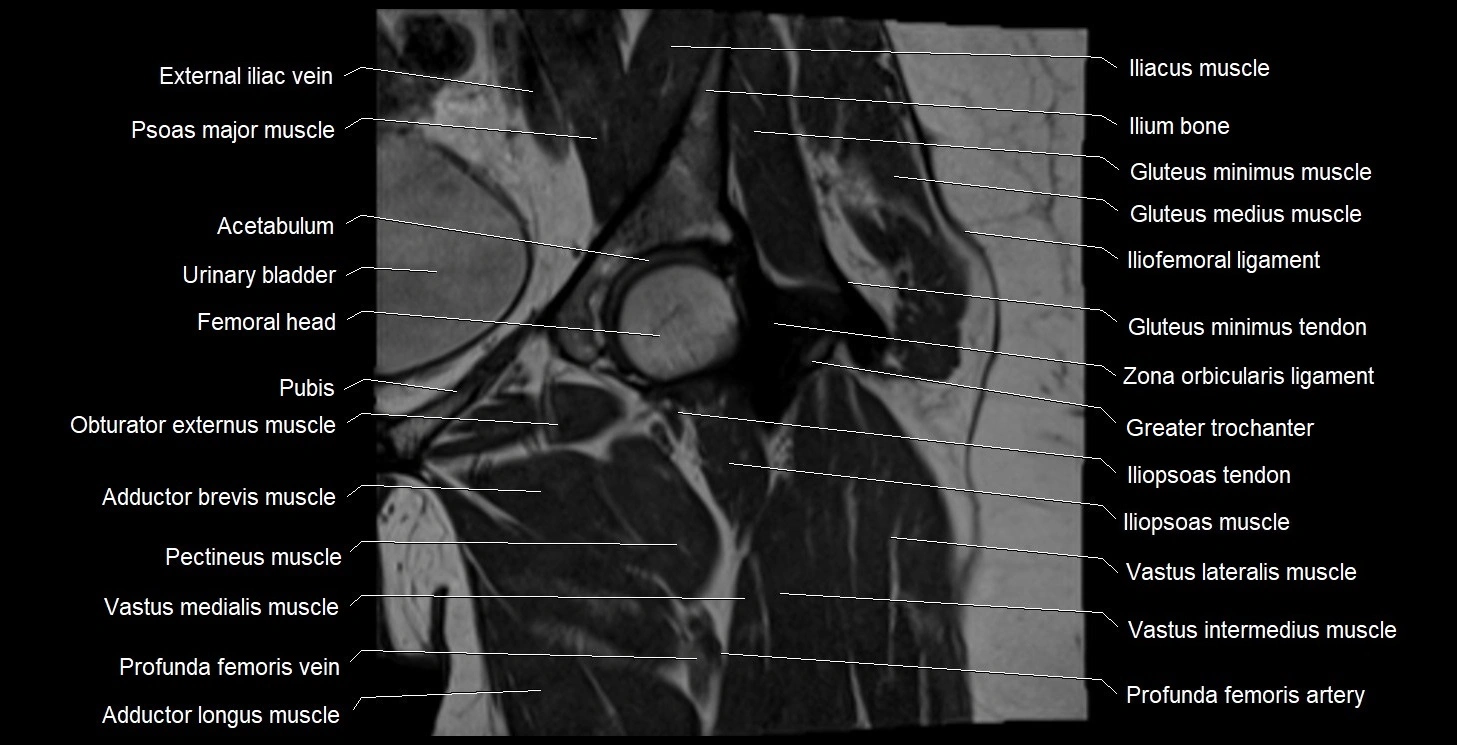

- Acetabulum

- Adductor brevis muscle

- Adductor longus muscle

- External iliac vein

- Gluteus medius muscle

- Gluteus minimus muscle

- Gluteus minimus tendon

- Greater trochanter

- Head of femur

- Iliofemoral ligament

- Iliopsoas muscle

- Iliopsoas tendon

- Ilium bone

- Neck of femur

- Obturator externus muscle

- Pectineus muscle

- Psoas major muscle

- Vastus intermedius muscle

- Vastus lateralis muscle

- Vastus medialis muscle

- Zona orbicularis ligament